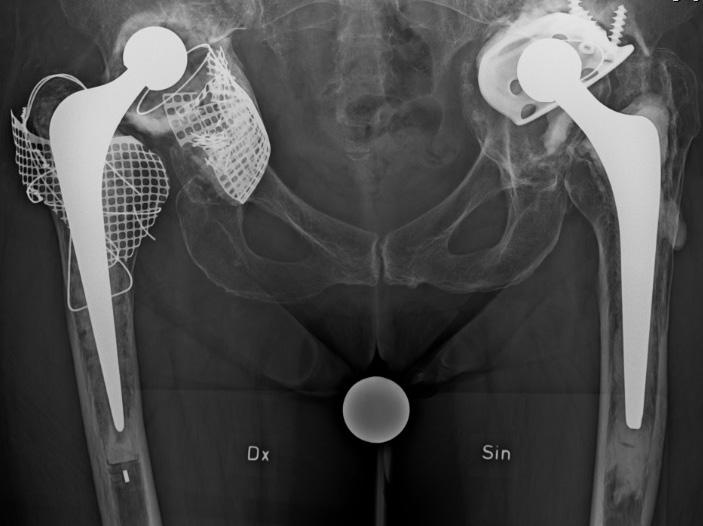

YTERSÄTTNINGSPROTESER I HÖFTLEDEN

Bakgrund: Unga och aktiva patienter har en ökad risk för protesrelaterade komplikationer. Det kan också uppstå svårigheter att rekonstruera en protesled på grund av att ben resecerats i samband med primäroperationen. Unga patienter med höftprotes vill kunna ägna sig åt krävande idrott utan att riskerat att höften hoppar ur led.

Hypotes: Grundtankarna är att 1: bevara patientens lårbenshuvud, 2: att resecera så lite ben som möjligt och 3: att skapa en stabil led genom att använda stora diametrar på ledhuvudet. Genom att använda leder med metall mot metall kan minimalt med ben reseceras på både ledhuvud och ledskål. Med tillkomst av nya tillverkningstekniker för metaller kan en ledprotes med mycket låg friktion skapas. Metall mot metall-leder har teoretiskt en lång hållbarhet.

Tidigare erfarenheter: De tidiga försöken med bland annat Wagnerpotesen fick snabbt överges på grund av komplikationer främst orsakade av cirkulationsrubbningar i lårbenshuvudet och snabb protesförslitning beroende på de stora friktionsytorna.

Resultat: De nya ytersättningsproteserna introducerades av främst McMinn och Amstutz strax efter sekelskiftet 2000 och fick ett betydande genomslag, inte minst som protes för unga och aktiva ”idrottsprotes” (bild till höger). Rapporter om komplikationer med höga nivåer av metalljoner, destruerande

mjukvävnad runt leden (pseudotumör) och collumfrakturer började dock relativt snart påverka entusiasmen.

En av tillverkarna drog 2010 in sin protes med omedelbar verkan. Men nästan 100 000 patienter hade då redan blivit opererade med denna protes. Härefter har metoden snabbt minskat i användning – även om vissa ”entusiaster” fortsätter att genomföra operationen. De vetenskapligt verifierade riskerna med ytersättningsprotes är;

1. Avaskulär nekros av collum/caput (bild). Detta kan leda till fraktur på lårbenshalsen.

Röntgen av osteolys, caputnekros och collumfraktur samt en ytersättningsprotes infälld i bild.

2. Pseudotumör – som i vissa fall kan bli mycket stor och destruera benet runt leden. Pseudotumör har kopplats till ökade koncentrationer av metalljoner i vävnaden kring protesen och i blodet. Pseudotumörer kan förekomma både hos patienter som erhållit ytersättningsprotes och sådana som opererats med andra helproteser med stort metallhuvud kombinerat ledskål i metall.

3. Höga nivåer av cirkulerande metalljoner (krom och kobolt) från ledens ytor.

Genom hårt driven marknadsföring främst via nätet träffar vi tyvärr fortfarande på patienter som är nyopererade med ytersättningsproteser – ofta i Belgien eller Holland – och som snabbt har drabbats av komplikationer. I allt för många fall har unga patienter drabbats av alvarliga och helt onödiga komplikationer. Patienter med metall mot metall-leder behöver dessutom följas avseende nivåer av metalljoner och utveckling av pseudotumör – vilket är mycket kostsamt och helt onödigt eftersom det finns betydligt säkrare alternativ.

PET-CT av ytersättningsprotes 1 vecka, 4 månader och 14 månader efter operationen. Pilarna visar en gradvis utveckling av caputnekros i den opererade höften. Gösta Ullmark, Gävle.

Ortopediskt Magasin pratar med Gunnar Flivik, docent vid ortopeden på Skånes Universitetssjukhus i Lund, om skräddarsydda implantat framtagna med 3D-printning för höftpatienter.

– När man gjort flera höftrevisioner på samma patient, det är stora bendefekter och inget verkar fungera, då är det dags att ta till patientspecifika, skräddarsydda implantat, baserat på datortomografiundersökning av patienten och tillverkade med hjälp av 3D-printning, förklarar Gunnar Flivik.

Dessa implantat har definitivt ändrat förutsättningarna för patienter som står inför stora krävande acetabulära revisioner. Det handlar om patientspecifika rekonstruktionsringar som överbryggar och fyller ut stora bäckendefekter och som man sedan kan fixera vanliga cupar i.

– Vi var först i Norden med att använda den här specifika tekniken med vår

Postoperativ röntgen av implantat efter resektion av chondrosarkom. Operationen görs av tumörortopederna i samarbete med artroplastikteamet.

första operation gjord 2012. Idag har vi på SUS gjort 30 operationer med den här typen av implantat, i Norden totalt drygt 100 och över hela världen är det ca 700 operationer gjorda. Så här långt ser våra resultat väldigt bra ut, inte minst med tanke på omfattningen av kirurgin och den känsliga patientkategorin.